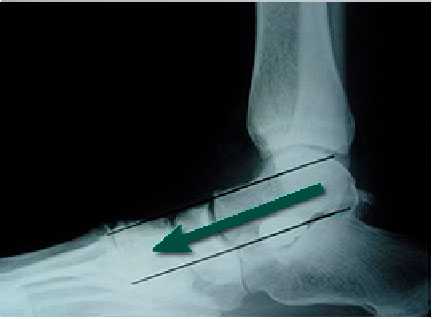

Рентгенограмма стопы в боковой проекции пациента с тяжелым плоскостопием. Данному пациенту в дополнение к перемещению сухожилия и остеотомии пяточной кости выполнен артродез среднего отдела стопы.

Рентгенограмма стопы пациента с тяжелым плоскостопием. Для эффективного восстановления формы и функции стопы в данном случае выполнен трехсуставной артродез стопы.